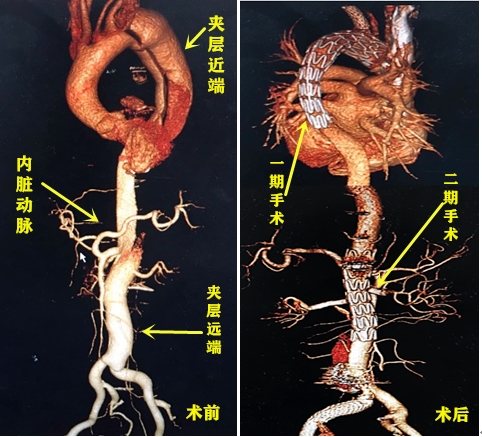

为了保障患者的治疗安全,决定将手术分为两次进行。一期手术在去年8月22日顺利完成,通过植入主动脉的覆膜支架来帮助近端的血管破口“堵漏”。为避免黄爷爷在术后发生截瘫,团队为其制定了一个恢复周期,二期手术被安排于今年6月进行。

崔驰介绍说,在本次手术中用到的是目前血管外科最先进的“微创开窗技术”,即利用前沿3D打印技术结合患者术前CTA影像,制作出与患者主动脉形态完全吻合的“血管模具”。医生根据模具形态预先在支架上开凿小孔,并在术中通过血管将支架送入,再将小孔逐个精准对位于内脏动脉,即可完成内脏动脉重建和远端血管破口的封堵。手术伤口约2cm、术中出血量仅几十毫升,精准操作之下实现了患者的最大化受益。